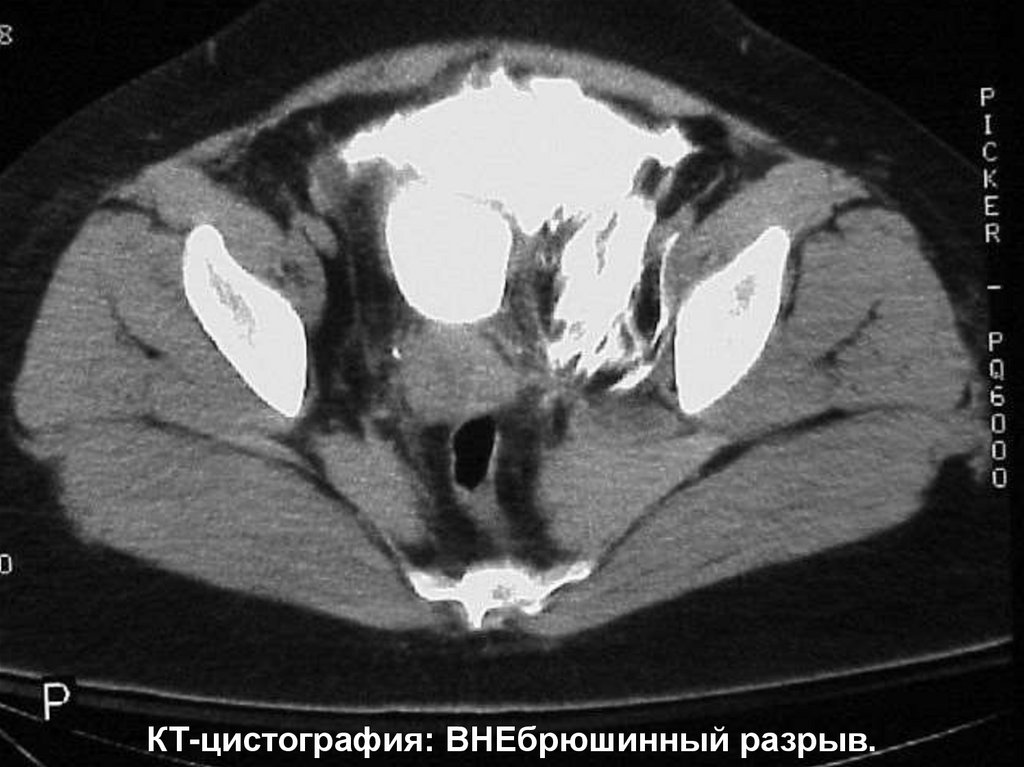

11.

КТ-цистография: ВНЕбрюшинный разрыв.